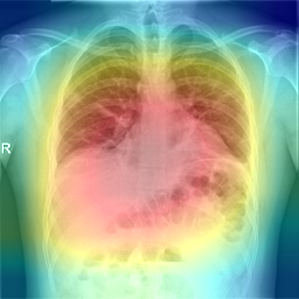

In order to compare the interpretability capacity of our model and the state-of-the-art models, we employ Grad-Cam [18] for heatmap visualizations on selected X-ray images. We show on a side-by-side basis how our model performs with superiority in Figures 4-7. We also observe that the addition of the attention block has a crucial role in focusing on the most relevant features in the images, which significantly assists the model during classification.